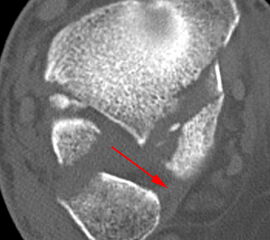

Liegt eine Fraktur des oberen Sprunggelenks vor, ist sowohl zur Entscheidung für ein konservatives oder operatives Vorgehen, als auch zur Operationsplanung, ein ausreichendes Verständnis der Fraktur und ihrer Morphologie notwendig. Insbesondere bei komplexen Verletzungen ist dafür die konventionelle Röntgenaufnahme in vielen Fällen nicht ausreichend. So konnten z.B. Black et al. zeigen, dass die operative Strategie zur Versorgung von OSG-Frakturen in 24% basierend auf einer zusätzlichen CT-Bildgebung relevant geändert wurden 7. Dies betraf die Lagerung, die Wahl des Zuganges und die Art der osteosynthetischen Versorgung. Besonders häufig änderte sich das Vorgehen bei Verletzungen des medialen (21%) und des posterioren Malleolus (15%). Darüber hinaus führten dislozierte (dislozierte Frakturen 31% vs. nicht-dislozierte Frakturen 20%) oder komplexe Frakturen (Trimalleolar-Frakturen 29% vs. Unimalleolar-Frakturen 10%) besonders häufig zu relevanten Änderungen des operativen Vorgehens. Die Computertomographie ist daher, insbesondere bei Bi- und Trimalleolar-Frakturen, essentiell für das Verständnis der Fraktur und somit für die Planung und Durchführung der Operation. In Abbildung 4 und 5 sind exemplarisch ein Röntgen- und ein CT Befund gegenübergestellt.

Seit einer Untersuchung von Nelson und Jensen aus dem Jahre 1940 wird allgemein akzeptiert, dass die Indikation zur Osteosynthese des Tibiahinterkantenfragments nur dann besteht, wenn die Größe mehr als ein Drittel (nach zahlreichen Autoren auch ein Viertel) der Gelenkfläche beträgt (Abbildung 15) 25. Dieses bis heute allgemeinakzeptierte Vorgehen basiert auf der Beobachtung von lediglich acht unterschiedlich versorgten Patienten. Seither gibt es keine weiteren klinischen Studien, die dieses Vorgehen stützen. Mittlerweile gibt es allerdings zunehmend Hinweise, dass bei der Versorgung des posterioren Malleolus viele andere Faktoren eine wichtige Rolle spielen 26. Da an der Tibiahinterkante das Lig. tibiofibulare posterius ansetzt (Abbildung 16), wird durch die offene Reposition und Stabilisierung die Integrität und die physiologische Spannung der hinteren Syndesmose rekonstruiert (Abbildung 17). Dies ist entscheidend für die anatomische Reposition der Fibula in der Tibiainzisur.

Es ist zu beachten, dass bei der Versorgung der Syndesmoseninstabilität bisher viele Fragen nicht eindeutig beantwortet sind. Dies beginnt mit der Auswahl des Testverfahrens zur Überprüfung der Instabilität und dem Nachweis der Korrekten Reposition der Fibula in der Inzisur. Auch die Wahl des Implantates, sowie die notwendige postoperative Bildgebung sind Gegenstand anhaltender Diskussionen. Bekannt ist, dass Syndesmosenverletzungen in bis zu 23% der OSG-Frakturen auftreten und dass die anatomische Reposition der distalen Fibula in die Tibiainzisur eine hohe prognostische Relevanz hat 33.  Allerdings ist die Kontrolle der Reposition durch die variable Form und Tiefe der Tibiainzisur nur anhand zweidimensionaler Röntgen-Aufnahmen intra-operativ erschwert. Die Tiefe der Inzisur variiert zwischen 1 mm und 7,5 mm und weist nur in 60-75% eine konkave Form auf 34. Auch die Wahl des Implantates ist Grund für andauernde Kontroversen. Standardmäßig erfolgt bisher in den meisten Kliniken die Versorgung mittels Stellschrauben-Osteosynthese. Allerdings konnten verschiedene Studien zeigen, dass die Fehl-Repositionsrate nach Stellschrauben-Versorgung höher lag als nach einer Versorgung mittels Tight Rope 3536. Auch, ob die postoperative CT-Bildgebung zur Stellungskontrolle notwendig ist und wenn ja, ob der Vergleich zum unverletzten Bein durchgeführt werden sollte, ist Gegenstand intensiver Diskussionen. Postoperativ wird eine insuffiziente Reposition in bis zu 38% beobachtet 33. Man muss aber vermuten, dass diese insbesondere mit der konventionellen Bildgebung nicht zuverlässig erkannt werden und somit ursächlich für persistierende Beschwerden sind. Bei knöchernen Syndesmosenausrissen an Fibula (Wagstaffe-Fragment) oder Tibia (Tubercule du Tillaux-Chaput) sollte eine direkte Versorgung mittels Schraubenosteosynthese oder mittels transossären Nähten angestrebt werden.